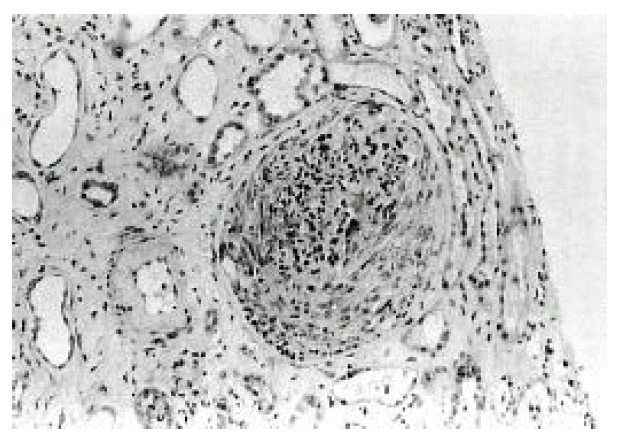

Figure 2.

Renal biopsy showing a crescent formation and a glomerulus with a cellular proliferation (H & E stain, ×200)

A 66-year-old man was admitted to Keimyung University Hospital because of decreased urine output and right upper quadrant pain. Seven years earlier, he had a Whipple’s operation for obstructive jaundice due to Ampulla of Vater cancer. At that time, the pathology report showed a moderately differentiated adenocarcinoma and biopsies of the regional lymph nodes showed no evidence of metastasis. At that time, renal function was normal and the urine contained no proteins or red cells. Two weeks before admission, the patient developed right upper quadrant dull pain, nausea, anorexia, myalgia, chills and fever. Four days prior to admission, he noticed gross hematuria, marked decrease in urine output and edema in lower extremities. On admission, his body temperature was 36.4°C and blood pressure was 110/60 mmHg. Daily urine output ranged 800–1200 mL. Face was puffy. He did not have icterus. His conjunctivae was slight anemic and revealed several petechial hemorrhages. Auscultation of the lung revealed bilateral basilar rales. No murmurs or frictions were heard. The liver was enlarged and tender. There was no splenomegaly or rash. There was marked costovertebral angle enderness. here was mild pretibial edema. Laboratory data on admission showed WBC 34,600/mm3, hemoglobin 8.3 g/dL, platelet count 95,000/mm3, BUN 16.4 mmol/L, serum creatinine 985,6 μmol/L, cholesterol 118 mg/dL, total bilirubin 3.4 mg/L, alkaline phosphatase 270 IU/L, SGPT 18 IU/L, and serum albumin 2.0 g/dL and creatinine clearance 2.5 ml/min. Urinalysis showed specific gravity 1.020, protein 2+, and urinary sediment containg two granular casts, many red blood cells and 10 white blood cells/HPF. The 24-hour urinary protein excretion was 2.4 gm and FENa was 1.7%. C3 level was 0.67 g/L (normal range: 0.8–1.2 g/L) and C4 level was 0.46 g/L (normal range: 0.2–2.5 g/L). Cryoglobulin was absent. The tests for hepatitis B and C, antinuclear antibody and rheumatoid factor were negative. Chest radiographs demonstrated bilateral perihilar pulmonary congestions. On admission, he was afebrile. He had obvious pulmonary edema as well as peripheral edema. Immediate hemodialysis resulted in a weight loss of 2 kg and respiratory improvement. Ultrasonographic examination of liver showed ill marginated cystic mass in left lobe. Computed tomography (CT) of the abdomen demonstrated 7×5cm sized multiple septated lower density lesions in medial segment of left lobe of the liver (Figure 1). Numerous blood cultures were negative. Initially the patient was treated with diuretics, albumin infusions and antibiotics (sulbactam/cefoperazone and aztreonam). On the 15th day, percutaneous needle biopsy of the kidney was performed. Light microscopy showed 17 glomeruli with two global sclerosis. The glomeruli showed endo-and extracapillary proliferation (Figure 2), with cellular crescents involving 25% of the glomeruli. The interstitium showed diffuse edema and no tubular necrosis. Immunofluorescent examination showed a diffuse granular staining with anti-IgG and anti-C3 along the capillary wall, and no staining with anti-IgM or anti-IgA (Figure 3). Needle aspiration of the liver was performed on the 19th hospital day, with the drainage of greenish pus material. Culture of the liver aspirates later grew Pseudomonas aeruginosa. Ticarcillin was given. The patient improved substantially. The levels of BUN and serum creatinine declined progressively and stabilized at 5.7 mmol/L and 176 μmol/L, respectively, by the 25th hospital day. One month after admission, the laboratory findings were : BUN 5.5 mmol/L, serum creatinine 176 μmol/L, hemoglobin 8.1g/dL. WBC 5,430/mm3 and platelet count 208,000/mm3. The 24-hour urinary protein excretion was 4.4 g/day. Follow-up CT showed almost complete resolution of previous abscess in the liver. He was discharged on the 40th hospital day with the serum creatinine level of 167 μmol/L.